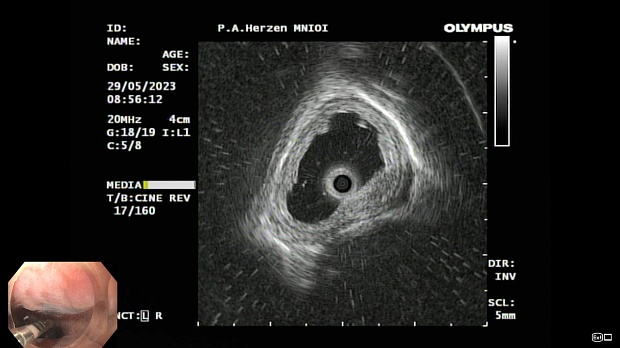

Иллюстрация №1: Эндофото. Сидероз нижней трети пищевода, осмотр в белом свете

Иллюстрация №3: Эндофото. Сидероз нижней трети пищевода, эндоскопическая ультрасонография

Согласно полученным данным - в среднегрудном и нижнегрудном отделах пищевода определялась проксимальная граница плоских неправильной формы поверхностных рубцов суммарной протяженностью до 8,0 см. На этом фоне в зонах поверхностных рубцов по задней полуокружности визуализировались участки гиперпигментации в темный цвет (Рис. 1). При исследовании в режиме Dual Focus было отмечено наличие мелких (до 0,001 см) черно-коричневых включений, расположенных субэпителиально - в строме слизистой оболочки, сливания их в единый конгломерат не определялось (Рис. 2). При эндосонографии с применением минидатчика с частотой сканирования 20МГц выявлено, что все слои стенки четко дифференцируются, не утолщены, в слизистой оболочки визуализированы мелких гиперэхогенные включения с эхотенями (Рис. 3).

В пищеводе в шейном его отделе на уровне 16 см от резцов циркулярно визуализированы единичные синюшные флебоэктазии размерами до 0.5 см. Дистальнее пищевод визуально не изменен до уровня 28 см от резцов, где определяется проксимальная граница плоских неправильной формы поверхностных рубцов, распространяющихся до уровня 36 см от резцов. На этом фоне в зонах поверхностных рубцов по задней полуокружности визуализированы участки гиперпигментации в черно-коричнеый цвет. При осмотре в режиме Near Focus с увеличением - между зон пигментации определяются расширенные капилляры типа II по Inoue-классификации. При биопсии отмечена десквамация плоского эпителия, визуализированы мелкие черно-коричневые включения в строме слизистой оболочки, размеры их до 0,001 см, сливания их в единый конгломерат не отмечается. При эндосонографии с датчиком 20Мгц в исследуемой зоне в слизистой оболочке определяются гиперэхогенные включения, в то время как в подслизистом слое - зоны со сниженной эхогенностью. При биопсии отмечается уплотнение ткани, однако истинной фрагментации не определяется. Уровень Z-линии совпадает с уровнем анатомического кардиоэзофагеального перехода. Розетка кардии эластичная, смыкается не полностью, расположена на уровне пищеводного отверстия диафрагмы.

Заключение: Эндоскопическая и эндосонографическая картина трудна для трактовки: следует дифференцировать сидероз слизистой оболочки пищевода на фоне постэрозивных рубцов и меланоз пищевода